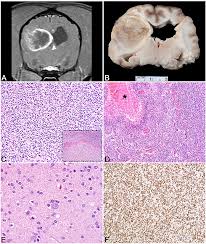

This was the brain tumor. Treatment for benign tumors usually require surgery. Common neurologic signs observed in animals with brain tumors include altered mentation (e.g. Meningioma is the most common type of brain tumor in both dogs and cats. What are the signs of a brain tumor?

If your dog is listing to the right or left and seems to be asymmetrical (i.e., leaning or stumbling when he tries to move,) it could indicate that a tumor is pressing on or stressing part of his brain used for movement. What are the signs of a brain tumor? Since these tumors are located inside the skull, they can cause pressure on the brain and sometimes invade the brain itself. Treatment for benign tumors usually require surgery. Benign tumors in dogs grow slowly and do not spread to or destroy the surrounding areas. For example, they might have seizures, problems balancing, or a change in their behaviour. These signs can also indicate vestibular disease and not a brain tumor. Specific signs will depend on where the tumor is located and may include a swollen paw, eye discharge or sores in the mouth. He may also develop brain cancer from tumors that have spread from other parts of the body into the brain. Seizures are the most common clinical sign in dogs. The diagnosis of a brain tumor in dogs typically starts with a thorough physical examination by your veterinarian (including a careful neurologic examination to look at the pupils, the response to light, the reflexes in the limbs, etc.). The most commonly observed clinical sign of a brain tumor in a dog is seizures. The signs of brain tumors can vary widely depending on where the tumor is located in the brain and also on its size.

The most common indication of a brain tumor in dogs is seizure, especially seizures that begin for the first time in a dog older than five years of age. Dog brain tumour final stages include all of the above signs continuing and progressing. There are many tests that will be carried out beginning with a taken history, a physical examination, and blood work. Since these tumors are located inside the skull, they can cause pressure on the brain and sometimes invade the brain itself. A brain tumour is just one possible cause for seizures.

If your dog is listing to the right or left and seems to be asymmetrical (i.e., leaning or stumbling when he tries to move,) it could indicate that a tumor is pressing on or stressing part of his brain used for movement. These types of seizures tend to start after the dog clocks five years. The most common indication of a brain tumor in dogs is seizure, especially seizures that begin for the first time in a dog older than five years of age. These signs can also indicate vestibular disease and not a brain tumor. Physical symptoms of a dog brain tumor signs a tumor may be impairing your dog's motor skills and bodily functioning are: A behavioral regression could follow this in your dog. The most common tumor types are called astrocytomas, oligodendrogliomas and meningiomas. Depending on the area of the brain the tumor is affecting, you might notice different symptoms and signs of brain tumors in dogs. For example, they might have seizures, problems balancing, or a change in their behaviour. How is the diagnosis made? What are the signs of a brain tumor? A brain tumour is just one possible cause for seizures. Regardless, prompt treatment is the key to giving your dog the best chance of survival.

Seizures can be general, affecting the whole brain causing a classic 'fit', or focal, just affecting one part of the brain, thus one part of the body. For example, they might have seizures, problems balancing, or a change in their behaviour. As a result, there's a wide range of symptoms that could potentially indicate a brain tumor, and those symptoms may appear suddenly or progress over a period of weeks or months. Common neurologic signs observed in animals with brain tumors include altered mentation (e.g. Specific signs will depend on where the tumor is located and may include a swollen paw, eye discharge or sores in the mouth. The most common tumor types are called astrocytomas, oligodendrogliomas and meningiomas. The life expectancy for dogs with a brain tumor can be difficult to answer as there are multiple factors which come into play. These signs can also indicate vestibular disease and not a brain tumor. Confusion and weakness, particularly favoring one side of the body, are other key signs to watch for. Some could live up to a year or more, while others may only have a few weeks remaining. The most commonly observed clinical sign of a brain tumor in a dog is seizures. Ataxia is a common symptom of brain tumor in dogs. Trouble walking or staying balanced